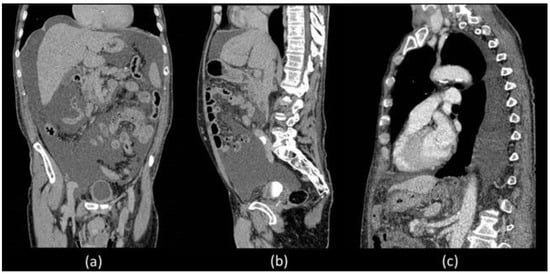

Unfortunately, he was readmitted 7 days later with abdominal distension and dyspnoea. During hospitalization, thorax and abdominal contrast-enhanced CT was performed which confirmed a massive ascites and described the presence of left pleural effusion without the presence of liver diseases (Figure 1).

Coronal (a) and sagittal (b) abdominal CECT showed massive ascites in supra and inframesocolic recesses. Non-hepatic diseases were recorded. (c) Sagittal thorax CECT demonstrated left pleural effusion.

In order to better assess the post-surgery pelvic region, abdominal MR was performed which did not show evidence of surgical injuries and liver diseases (Figure 2).

MR T1 weighted (a) axial section of the liver did not show diseases but confirmed the presence of massive fluid effusion, visible in the supra and submesocholic space and also in the coronal (b) and sagittal images (c).